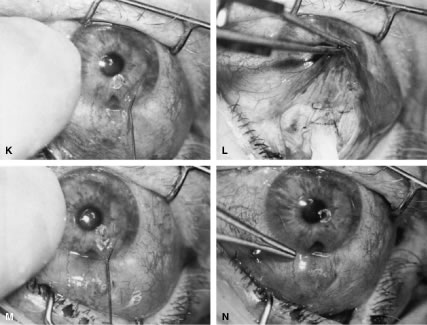

After the iridectomy is complete, the iris usually will return spontaneously into the anterior chamber unless it has suffered damage as a result of high pressure (as occurs in severe attacks of angle closure glaucoma). In patients with a reactive sphincter, it usually is necessary only to release the iris from the grasp of the incision. The iris can be stroked into position with the use of a blunt instrument on the corneal surface. Attempting to reposit the iris by directing a stream of irrigating solution into the incision is not recommended; the solution may enter the posterior chamber, forcing even more iris out of the incision. If the surgeon has difficulty restoring the iris to its proper position, injection through the previously placed paracentesis track of freshly mixed acetylcholine usually will solve the problem. In the eye with a dilated fixed pupil and a flaccid iris, it often is preferable to perform a sector iridectomy. Once the pupil is entirely round, the suture placed previously in the corneoscleral incision can be pulled up and secured promptly. Injecting balanced salt or acetylcholine solution through the previously placed paracentesis can deepen the chamber. In patients who have had recent angle-closure attacks and in whom peripheral anterior synechiae may be newly developed, forceful deepening of the anterior chamber at this point may tear open the synechiae and restore normal function of the anterior chamber. The procedure of chamber deepening must be done cautiously, with careful monitoring of IOP. A gonioprism, such as the Zeiss four-mirror lens, can be used with an operating microscope to monitor the effect on anterior chamber angle. At the close of the procedure, the pupil should be round, the chamber deep, and the incision sufficiently closed that there is no leakage. The IOP should be approximately 15 to 30 mm Hg, being raised to that level by injection through the keratostomy. Such a pressure may help prevent subsequent choroidal detachment and allows the integrity of the incision to be tested. If the corneoscleral incision has been properly placed and sutured, there should be minimal transient astigmatism. Vision should return to the preoperative level within several days. If the eye is inflamed, it usually is helpful to instill a short-acting cycloplegic agent such as cyclopentolate. Furthermore, the surgeon may give a subconjunctival injection of corticosteroid, although it rarely is necessary to do so. An antibiotic ointment and a light patch usually are applied until the facial nerve block has worn off. If there is a reasonable chance that the patient will need a filtration procedure at a later date, then the surgical procedure is modified to perform the iridectomy through clear cornea, rather than under a fornix-based flap. The technique is almost exactly the same, with the obvious exception that the incision is placed through clear cornea. Postoperative Care In almost all instances, iridectomy can be performed as an outpatient procedure. However, when associated with severe pain or when the attack of angle closure has been difficult to stop and has required extensive usage of carbonic anhydrase inhibitors and osmotic agents, admission of the patient to the hospital may be justified. Especially in older and infirm patients, the general state of health must be monitored carefully. It is important to verify that the patient has not become overly dehydrated or experienced an attack of congestive failure. The eye patch usually is removed from the treated eye as soon as the facial nerve block has worn off. If the procedure is done on an outpatient basis, a patch and shield may be left in place until the patient returns the next day for the first postoperative visit. A drop containing a corticosteroid can be used topically three or four times a day until the inflammatory response has disappeared, usually 4 to 7 days. Careful attention must be paid to the state of the pupil. The development of posterior synechiae is an important and usually unnecessary complication. Although it is not clear that posterior synechiae predispose the patient to the development of cataract, the presence of such adhesions makes extracapsular cataract extraction more difficult. Because many patients with angle-closure glaucoma will later have cataract extraction, the development of such adhesions may jeopardize the long-term visual result. Furthermore, inability of the pupil to dilate in the dark may limit the patient's visual function, especially in conjunction with a developing cataract. In most cases, dilating drops are used routinely until the inflammatory response has worn off. One acceptable program is to use tropicamide 1% at sufficient intervals to ensure that the pupil is dilated adequately for a period of approximately 1 week. The medication can be continued at bedtime for 2 to 3 weeks, or even longer, until it is certain that the inflammatory response has disappeared. Many patients are given pilocarpine preoperatively. There is a tendency to continue the administration of pilocarpine postoperatively, especially when control of IOP has been difficult. This practice should be discouraged. Pilocarpine will predispose patients to posterior synechiae and should be avoided if possible. The drug of choice for pressure control usually is topical epinephrine, a β-blocker, or epinephrine plus a β-blocker. If these two agents are not adequate, a carbonic anhydrase inhibitor can be used until the eye is entirely quiet, at which time pilocarpine can be reinstituted. In such cases, however, care should be taken to dilate the pupil periodically to prevent the development of posterior synechiae. Some surgeons may be reluctant to use dilating drops for fear of inducing angle closure. This possibility exists, but it is uncommon. Furthermore, it is preferable to know immediately whether the iridectomy has eliminated the possibility of angle closure caused by papillary dilatation. Therefore, this concern is an additional reason to use cycloplegic agents in the immediate postoperative period. Because of the possibility of an increase in IOP after dilatation, however, IOP should be checked carefully after the use of the cycloplegic agent. In addition, IOP should be monitored carefully during the initial postoperative period. Pressure spikes are not uncommon. These spikes are of little concern if the optic nerve is healthy. However, in patients with advanced glaucomatous nerve damage, such pressure spikes can be devastating; they should be avoided if possible. Postoperative evaluations ordinarily are made on the first postoperative day, after 1 week, and after 1 month. If a problem with the control of IOP is suspected, visual fields and disc photographs should be obtained. Complications The most serious complication after iridectomy is malignant glaucoma (aqueous misdirection, ciliary block glaucoma). Eyes predisposed to this complication are those with small anterior segments, typically seen in patients with marked hyperopia or small globes. Furthermore, there is some indication that eyes with high IOP preoperatively may be predisposed as well. Patients who have had an attack of malignant glaucoma in one eye are likely to have the same complication in the second eye. GUARDED FILTRATION PROCEDURES (TRABECULECTOMY) What traditionally has been called a trabeculectomy has become the standard filtration type of surgery for most cases of open-angle glaucoma. The name is a generic one, describing a wide variety of surgical methods, some substantively different from others.46–50 A goal of the original procedure was to allow filtration out of the cut ends of Schlemm's canal. In most cases, this mechanism does not appear to be the actual reason for the decrease in IOP that usually follows. Another theoretic explanation for its pressure-lowering effect, direct access of aqueous humor to the collector channels, bypassing diseased trabecular meshwork or Schlemm's canal, may be the actual mechanism for pressure reduction in a few cases. Exploration of the operative site does not disclose any area of gross filtration in some patients who have effective pressure lowering after surgery. It is likely that in such cases, aqueous humor exits into the collector channels or perhaps through the thinned scleral tissue. In most cases, the mechanism responsible for lowering IOP after guarded filtration procedure is a through-and-through fistula connecting the anterior chamber with the subconjunctival space. As such, the word trabeculectomy is a misnomer. Complete success is possible without removing trabecular tissue. Lamellar sclerokeratectomy would be a more accurately descriptive title, and it has been suggested in the past. However, the term is cumbersome and to some extent, inaccurate, because sclera is not always removed. Because the term trabeculectomy is a significant misnomer, we rarely use it in this chapter. The procedure performed currently functions as a filtration procedure; consequently, it is appropriately called a filtration procedure. When it is performed so that the filtering area is at least partially protected in an attempt to control the amount of filtration, the term guarded filtration procedure is appropriate and is used in this chapter. Consideration of how the operation actually works is not of purely academic interest; it materially affects how the surgery is performed and influences the final result. Patients with gross fistulas with filtering blebs resembling those seen with operations that were popular in the past, such as the corneoscleral trephine, usually achieve lower IOP than patients in whom the filtering bleb is thicker, more posterior, and less cystic. Furthermore, the thinner, polycystic bleb probably lasts longer, providing more years of low IOP. Consequently, if the surgeon wants to obtain IOP that is as low as possible, the guarded filtration procedure should be designed to produce gross filtration. Such a goal has its costs, however. A general principle of glaucoma surgery is that every millimeter of pressure-lowering effect has a price. This principle applies to guarded filtration procedure; the complication rate with procedures designed to produce gross filtration and lower IOP is greater than that with procedures that are more completely guarded and in which a higher final IOP is considered satisfactory, as discussed in detail in the first section of this chapter. The surgeon must carefully consider the major goal of the surgery being planned. For example, for the patient who has uncontrollable angle-closure glaucoma and is predisposed to flat chamber or even malignant glaucoma, the surgeon probably will fashion the scleral flap and suture it in place so that leakage is minimal. On the other hand, for a patient with high myopia with glaucoma that is progressive at a pressure level of 14 mm Hg, the surgeon probably will want to make the flap thin or ensure that there is leakage around the edge of the flap, or both, to have the greatest likelihood of gross filtration with a low final IOP. Factors predisposing patients to the final level of IOP are shown in Tables 14, 17, and 18. As shown in these tables, the more the surgical procedure mimics the classic Elliot corneoscleral trephine, the more reasonable to expect a final low IOP. Also, there is more likelihood of flat anterior chamber, choroidal detachment, cataract development, and a thin cystic bleb predisposing to endophthalmitis. Several modifications have been suggested for achieving a low final IOP with a reduced incidence of side effects. These include the placement of sutures so that they can be released easily in the postoperative period27,51–53 and the transconjunctival cutting of sutures postoperatively with a laser.54–57 These techniques are discussed later in this chapter. In routine cases, we prefer a limbus-based flap (Fig. 13). The development of this type of flap is only slightly more difficult than fashioning a fornix-based flap (see Fig. 11), but its advantages are significant. Compared with procedures performed with a fornix-based flap, the limbus-based operation is more likely to eliminate problems with postoperative leakage through the conjunctiva. In contrast, leakage at the cut edge of the conjunctiva of a fornix-based flap is common in the immediate postoperative period. Furthermore, cooperation under the limbus-based flap tends to be easier than with the procedure performed with the fornix-based flap. In addition, and of great importance, localized deformation of the wound in the immediate postoperative period for the purpose of encouraging filtration is performed more easily and safely when the radial grooves are covered with a limbus-based rather than a fornix-based flap. Because we often use this procedure [the Carlo Traverso maneuver (CTM)],58 the security afforded by the limbus-based flap is welcome. Thus, in most cases, the limbus-based flap is preferred. An exception is the case in which previous filtration surgery has failed and in which development of a limbus-based flap appears unjustifiably difficult and risky. Preoperative Care A careful history should be taken to determine whether systemic medical issues may affect the operative or postoperative course. For example, breathing problems and spinal arthritis may prevent the patient from lying completely flat. Chronic coughing or constipation with straining may increase the risk of postoperative suprachoroidal hemorrhage. Other relevant information includes what allergies are present and if the patient has a proclivity to excessive bleeding. Bleeding studies, such as prothrombin time, platelet count, and, in some cases, bleeding time, are appropriate in certain cases. Patients who are taking aspirin should not do so at least a week preoperatively, if possible. Similarly, anticoagulants should be discontinued long enough preoperatively to allow the coagulation characteristics to return to satisfactory levels. The eye should be as quiet as possible. Long-acting miotics, such as echothiophate, should be discontinued at least 3 weeks before surgery. If possible, pilocarpine or other short-acting miotics also should be discontinued long enough before surgery to allow their effect to wear off. Any signs of medication allergy may warrant discontinuation of the offending agent and sometimes preoperative topical steroids to quiet the inflammation, reducing intraoperative bleeding and postoperative scarring. The purpose of the surgery must be clear to the patient and the surgeon (see Table 1). Full discussion of the reasons for considering the surgery is essential, including alternative therapies and complications. Patients must understand that the usual goal of surgery is not improved visual acuity; visual acuity probably will be different and may be worse after the operation. Postoperative care must be discussed before surgery, with patients having a clear understanding of the need for continuing, careful monitoring of their condition. If it will be difficult for the patient to return to the operating surgeon, other arrangements that are satisfactory to both patient and surgeon must be made before the operation. Before the patient is sedated or anesthetized, the surgeon should again ensure that the patient's expectations and anticipations are realistic. Anesthesia Depending on the patient, surgeon, and procedure, anesthesia may range from general endotracheal anesthesia to topical agents alone. General anesthesia is reserved for patients unable to cooperate and hold still for the duration of the procedure. Retrobulbar or peribulbar injection of short- and medium-acting anesthetics, such as lidocaine and mepivacaine, with or without hyaluronidase are usually adequate. Some surgeons do not include hyaluronidase in the retrobulbar block because it may make the subconjunctival tissues boggy, complicating the surgery and making evaluation of the postoperative bleb more difficult. A facial block, such as a modified O'Brien facial nerve block,45 with approximately 10 ml of a short-acting agent, such as lidocaine or mepivacaine, may reduce lid squeezing. Most patients have only light sedation, such as 4 to 6 mg intravenous diazepam (Valium). In many cases, no sedation is necessary. Surgeons anticipating shorter, routine cases with cooperative patients may be comfortable with topical anesthesia, such as lidocaine jelly and topical tetracaine. If an iridectomy is planned, topical anesthesia may be supplemented with intracameral (nonpreserved) lidocaine 1%. Intracameral lidocaine may result in dilation of pupil, necessitating intracameral miotics before the iridectomy to prevent accidentally large iridectomies. We prefer to perform guarded filtration procedures with a modified O'Brien facial nerve blocky with approximately 10 ml of a short-acting agent, such as lidocaine or mepivacaine, in addition to a retrobulbar block with the same agent. Hyaluronidase is not included in the retrobulbar block because it tends to make the subconjunctival tissues boggy, complicating the surgery and making evaluation of the postoperative bleb more difficult. Most patients have only light sedation, such as 4 to 6 mg intravenous diazepam. In many cases, no sedation is necessary. Many patients are older, and in some, the only eye with useful vision is having surgery; therefore, the sooner the patient can be completely ambulatory after surgery, the better. In addition, in most cases, the goal of surgery is to develop a functional fistula, so it probably is helpful to remove the patch as soon as possible after surgery to encourage blinking and automassage. In some instances, especially with topical anesthesia, it is not necessary to apply a patch at all. In addition, rapid ambulation helps to ensure that the patient maintains a posture that prevents blood from settling in the area of the procedure. The use of short-acting agents and minimal sedation encourages prompt return to full normal function, an important consideration in the older person with sensory deprivation. Operative Technique The limbus-based conjunctival flap should be developed as far superiorly in the superior fornix as possible (Figs. 13 and 14). The conjunctival incision should be sufficiently far posteriorly that it involves the thick tissue overlying the superior rectus muscle; if it is made more anteriorly, the likelihood of leakage through the incision increases. This leakage is especially a problem when agents specifically used to combat postsurgical scarring are employed. Toothed forceps, or even serrated forceps with indentations that are sharp enough to cut the conjunctiva, should not be employed. On the other hand, a common error is to forget the normal elasticity of the conjunctiva and consequently to neglect to stretch the tissue sufficiently to permit clear identification of the edges of the incisions. This problem is a special concern with Tenon's capsule, which tends to retract out of the operative field, and may be overlooked unless specific attention is paid to bringing it into view. To facilitate a posterior incision, a superior rectus bridle suture may be placed and gently affixed to the drape. A second alternative is the corneal traction suture. A 7-0 Vicryl suture is placed through the peripheral cornea, approximately 0.5 to 1.0 mm from the limbus. The suture should be placed at least ½, but not full thickness, with plane of the spatulated needle parallel to the surface of the cornea in midbite, so that the cutting sides of the suture do not create tracks that may facilitate cheesewiring through the cornea. The eye is then rotated inferiorly, the suture entry and exit from the cornea checked for leakage indicative of an inadvertent full thickness passage, and the suture affixed to the drape with two pieces of tape, folding the suture of the first to prevent slippage. Sterile adhesive medication labels work well. The incision in the conjunctiva and Tenon's capsule should be long enough to permit easy retraction of the tissue toward the limbus, providing good visibility. A 10-mm incision is average. It is better to have the incision longer than shorter. If the initial incision is made directly over the insertion of the superior rectus muscle, it should not be carried deep into the tissue, because the muscle could be cut. Rather, the edge of Tenon's capsule and conjunctival tissue should be held firmly, and the underlying tissue separated with blunt dissection. The scissors should be tilted anteriorly toward the limbus to avoid the underlying muscle and the rich vascular network surrounding it. The blunt dissection is continued until Tenon's capsule is completely incised. A second approach is to make the incision in the supertemporal or supernasal quadrant, 8 mm or more posterior to the limbus, through conjunctiva and Tenon's capsule down to bare sclera. This approach avoids the risk of immediate damage to the muscle with bleeding. The scissors are then used bluntly spread and dissect the plane between Tenon's capsule and the sclera horizontally, parallel to the limbus, over the superior rectus. One blade of the scissors is then placed above the conjunctiva, and one beneath Tenon's and the wound enlarge parallel to the limbus. As the incision is enlarged, traction on the internal blade of the scissors away from the globe stretches the tissues over that blade, allowing careful inspection. Before making this enlargement of the wound, the surgeon must ascertain that the superior rectus is not within the tissue to be cut by the scissors. Tenon's capsule, with its conjunctiva, is spread anteriorly over the cornea to give the best view possible of the corneal scleral sulcus. In almost all instances, there is a thin layer of episclera remaining. This layer is grasped and elevated forcibly, permitting development of a 2 × 2-mm buttonhole, through which the bare sclera is easily visible. This episcleral tissue is markedly adherent. The buttonhole should be extended approximately 5 mm temporally and laterally. The forceps are used to grasp the edge of this deep episcleral tissue, and pull it anteriorly and inferiorly, so the surgeon can clean down to bare sclera anteriorly to the corneoscleral sulcus. The sulcus is not readily visible until the episcleral tissue has been reflected from it. In fact, it probably is the single most important landmark with regard to filtration surgery. As seen in Figure 4, the conjunctiva inserts just anteriorly to the corneoscleral sulcus. Dissection to that point can be carried out with relative ease, and with meticulous technique, even 1 mm or so anterior to the groove. More anterior to that, conjunctiva has metamorphosed into the epithelium of the cornea, and attempts to develop a conjunctival flap over the cornea itself are doomed to failure. Furthermore, the trabecular meshwork usually lies near the corneoscleral sulcus. In large eyes, which are common in myopes, a perpendicular incision just anterior to the corneoscleral sulcus would enter the anterior chamber well anterior to the iris root. In contrast, in small eyes, which are found in most hyperopes, an incision at the same point also would enter the anterior chamber but just in front of the iris root. When these eyes have extensive peripheral synechiae, an incision made with a sharp blade through the corneoscleral sulcus will penetrate into the posterior chamber, which obviously is not the location for most glaucoma procedures. Consequently, in small eyes with small anterior segments, especially in association with angle closure, the surgeon must place the corneoscleral incision more anteriorly than usual and be certain that the incision actually is entering the anterior chamber. In such cases, it may be necessary to shelve the incision anteriorly. This problem clearly affects patients with acute or chronic primary angle-closure glaucoma. We prefer to clean the conjunctiva meticulously until no fibers are crossing the corneoscleral sulcus. The most effective method is to use a no. 67 Beaver blade held at a 45-degree angle from the direction of the incision. Only the pointed tip is used to cut the tissue (see Fig. 13A). The dissection is continued anteriorly until the conjunctiva can no longer be cleaned further anteriorly. The corneoscleral sulcus should be free of fibers for a width of approximately 4 to 5 mm. Partial cleaning of the area posterior to the corneoscleral sulcus can be accomplished in a variety of ways, including grasping the Tenon's episclera and pulling it anteriorly and inferiorly, scraping the surface of the sclera in a semiblunt fashion with the edge of the blade, and pushing the tissue with the tip of a Weck-cell sponge (Xomed-Treace, Jacksonville, FL) or similar dry sponge. Such techniques almost always are only preparatory, and they do not clean the sulcus adequately. We emphasize this point because a frequent cause of failure of filtration procedures is blockage of the site of attempted filtration as the result of an excessively posterior incision, and the usual cause for an excessively posterior incision is failure to reflect the conjunctiva-Tenon's episclera sufficiently anteriorly. Some surgeons excise Tenon's capsule, especially where it appears to be redundant or particularly profuse. This practice is thought to increase the rate of success and to result in a thinner, more cystic conjunctival filtration bleb. Few studies have evaluated the advantages and disadvantages of this technique. However, it has the disadvantage of predisposition to a thinner, more fragile covering to the filtering bleb, with a greater incidence of postoperative complications, and it does not appear to result in lower IOP.59,60 A fornix-based approach, beginning with a peritomy, may also be used. The conjunctiva can be cleaned from the limbus by making an incision directly at the limbus at approximately the 11 o'clock position and performing a peritomy clockwise to approximately the 1 o'clock position (see Fig. 11). The addition of a relaxing incision at the 11 o'clock position allows better visibility and improves the closure. The limbal area is cleaned meticulously, and the conjunctival-Tenon's tissue is undermined to facilitate final closure of the fornix-based flap. The corneal epithelium directly at the limbus between the 11 and 1 o'clock positions should be removed 1 mm anterior to the limbus. Wet-field cautery is an excellent instrument for this. Care should be taken to test the power level of the cautery on the sclera or gently at the limbus first, to prevent unintended thermal damage to the cornea. High cautery settings may thus create astigmatism, but this usually reverses in days to weeks during the postoperative period. After the limbal area has been meticulously cleaned, either with a fornix-based or a limbus-based flap, light cautery outlines the position of the scleral flap (Fig. 15B). The shape of the flap is unimportant but in the routine case. We prefer one that is approximately 2 mm wide circumferentially and 3 mm long radially. This rectangular flap is easy to dissect and involves relatively little scleral tissue. A no. 67 Beaver blade is used to incise the sclera in the area outlined by the cautery. This incision should be at least half and preferably two thirds the thickness of the sclera. Magnification of the operating microscope usually is increased during the creation of the scleral flap. If the surgeon is right handed, the right-hand posterior corner of the scleral flap is grasped with a forceps such as the Pierce-Hoskins forceps. This instrument has indentations but no teeth and, therefore, is not likely to penetrate or tear the scleral flap. Even in cases in which the surgeon wishes to develop a thin scleral flap, it is preferable to start the dissection with a thick flap, at least one half the scleral thickness (see Fig. 13C). As the surgeon proceeds, the flap can be thinned to the proper thickness. The no. 67 Beaver blade may be used to dissect the flap. The knife should be held as parallel to the brow as possible, because this position facilitates dissection of the flap (see Fig. 15D). Finer, sharper “superblades” are useful when making very small scleral flaps. The thickness of the flap must be monitored carefully as it is developed. The surgeon should be careful never to dissect blindly but always must see the tip of the knife. Flipping the flap forward and back, so that the surgeon sees the outside and then the inside, can help in estimating the thickness of the sclera. The assistant should be diligent in sponging to keep the view of the dissection as clear as possible. We prefer to keep the scleral flap dry rather than to irrigate it; irrigation tends to hide the landmarks at the depth of the flap. Firm traction should be placed on the scleral flap that is being developed so that cutting is performed against traction. The flap is extended for at least 1 mm and preferably 2 mm anterior to the junction of the white sclera with a clear cornea (see Fig. 15E). Once the flap has been developed, and before the anterior chamber is entered, a paracentesis is formed with a short, sharp, disposable 25-gauge needle (see Fig. 5). We believe that the placement of this paracentesis track is vitally important. An alternative method is a stab type, uniplanar, temporal paracentesis. The stab-type paracentesis tends to leak more as balanced salt solution is instilled, which may make evaluation of fistula outflow more difficult. However, this paracentesis is more easily accessed, both intraoperatively and postoperatively and may be helpful if postoperative anterior chamber reformation is necessary. The anterior chamber is entered by incising through the sclera in a radial fashion, along the right-hand line of radially placed cautery. Multiple light scratches are placed, and the blade is kept vertical so that entry will be as close as possible to the anterior extent of the scleral flap. A sharp blade such as a diamond knife or superblade can be employed, but unless used with a guard, these blades are likely to penetrate into the iris. These sharper, more pointed blades make it possible to enter more anteriorly, which is a real advantage. But they must be used cautiously to avoid damage to the iris and lens, with subsequent development of cataract. The incision is made long enough so that its posterior edge is just posterior to the junction between the white sclera and the clear cornea. If the posterior extent of the incision is not long enough at the time of entry, the incision is lengthened. Vannas scissors are placed into the anterior chamber, with the surgeon making certain that the tip neither penetrates into the iris nor splits the sclera. This entry is assisted by lifting the area to be excised with a fine forceps, such as a Pierce-Hoskins forceps, and depressing the bed of the sclera with the edge of the Vannas scissors. The scissors must not be directed in an angled fashion so that they extend through the iris into the lens and underlying zonules. After the radial groove has been made, the block must be excised. There are advantages to cutting the anterior aspect of the block first, and advantages to cutting the posterior edge of the block first. To some extent, the method that is used depends on each eye and what occurs at the time of the surgery. Once the Vannas scissors is placed so that one blade is definitely in the anterior chamber, it can be moved anteriorly as far as possible so that it pushes firmly against the base of the scleral flap, where it is attached to the cornea. In the right eye, it usually is easier to use the right hand to hold the Vannas scissors. The left hand is used to fix the sclera at the posterior edge of the bed. The left hand pulls the globe superiorly in the direction of the brow, and the right hand pushes the Vannas scissors inferiorly toward the nose. The goal is to ensure that the section is placed as far anteriorly as possible, so that no ledge of cornea will be left. The blade of the Vannas scissors should be held exactly perpendicular to the cornea so that the cut is not shelved. The outer blade should be directly over the inner blade, as shown in Figure 15G. Once the anterior aspect of the block has been cut, the fixation on the posterior edge of the bed is released. The assistant who is holding the scleral flap anteriorly to ensure adequate visualization continues to hold the flap firmly. The left hand holds the anterior edge of the block and pulls it anteriorly (inferiorly) toward the nose. The Vannas scissors move posteriorly (superiorly) toward the brow, and the posterior edge of the block is incised. Again, the surgeon holds the scissors absolutely vertically so that the sclera will not be cut. Just as the anterior aspect of the block was incised all the way to the radial groove, the posterior block is incised all the way to the nasal radial groove. The surgeon changes hands, holding the Pierce Hoskins forceps in the right hand and the Vannas scissors in the left hand. The block is held with the right hand and amputated with the Vannas scissors, leaving the desired amount of ledge, usually 0.25 to 0.5 mm. When the block is removed, it should be inspected (see Fig. 15H). If it is not exactly rectangular with edges that are completely unshelved, then it has not been taken properly. The surgeon should note the error so that it can be corrected at the next surgical procedure. The corneosclera to be excised does not include sclera posterior to the scleral spur. Thus, there is no chance of performing a cyclodialysis and much less of a chance of injuring the large vessels that form such a rich plexus where the ciliary body attaches to the scleral spur. A second approach to anterior chamber entry and ostomy creation is to use a sharp blade to make an incision parallel to the iris at the far anterior extent flap bed, under the flap. Keeping the blade parallel to iris, entering similar to the creation of the phaco-tunnel, reduces the risk of damage to the lens and iris. A sclerocorneal punch, such as a Kelly-Descemet punch, is then introduced parallel to the iris, under the flap, through the incision. The punch is then rotated vertically so that it is perpendicular to the bed of the flap. The punch is then used to make several bites, usually near the temporal side of the flap bed, to create an ostomy. After each bite the punch is removed and the excised piece is wiped off with a sponge, and the punch reintroduced. Experience with the punch and care not to use excessive posterior pressure allows for the gentle creation of an ostomy of the desired dimensions with sharp, vertical edges. How much ledge the surgeon wishes to leave and how thin the surgeon wishes to fashion the scleral flap should have been determined carefully before surgery. These decisions will depend on the desired postoperative result (see Table 16). The thinner the flap, the lower the pressure; the smaller the ledge, the greater the likelihood of postoperative flat anterior chamber. An iridectomy is performed (see Fig. 15I). To ensure that the iris tissue does not plug the guarded filtration procedure site, the iridectomy should be large enough so that no edge of the iris is visible through the area of excised sclera. The scleral flap is sutured in place with 10-0 nylon. The suture is placed at a 45-degree angle to both the posterior and the radial edges, so that as the suture is tightened, the scleral flap will return to its proper position. An additional suture is placed at the other posterior corner (see Fig. 15J). Scleral flap sutures should be ½ to 2/3 thickness through the peripheral ½ mm of the flap. This reduces full-thickness holes through the flap that may allow excessive leakage. Longer bites on the scleral side allow easier suture isolation and viewing for possible postoperative laser suture lysis. Unless it is clear that there has been much scleral contraction and that the scleral flap has not closed adequately, at this point, the anterior chamber is filled with balanced salt solution through the previously placed paracentesis (see Fig. 15K). The surgeon monitors carefully the IOP with a finger placed on the cornea. If the anterior chamber cannot be formed readily, then additional sutures are placed until that can be achieved (see Fig. 15L). If the anterior chamber forms readily and the globe becomes firm, the surgeon tests the area of the procedure with sponges to determine whether fluid actually can leak through the radial edges (see Fig. 15L). Leakage through the posterior edge of the flap is undesirable because that portion almost always will scar closed, at which time the procedure will fail. Leakage, minimal or marked, through the radial incisions is the surgeon's goal. The amount of leakage is adjusted appropriately by applying cautery to shrink the edges of the radial incision or by placing additional sutures. It has not been determined whether the actual amount of leakage of aqueous humor through the sclera affects the final level of IOP. However, it certainly affects the immediate postoperative course, and it probably affects the final IOP. When leakage is marked, so that the anterior chamber collapses spontaneously, the eye is predisposed to flat anterior chamber and hypotony, two undesirable postoperative complications. When there is no leakage, the eye is predisposed to excessive elevation of IOP postoperatively; although this elevation is an undesirable complication, in almost all cases, it can be handled by removing a releasable suture or cutting a laserable suture. We prefer to close the scleral flap sufficiently tight so that when balanced salt solution is injected through the paracentesis, the IOP will be raised to approximately 30 to 40 mm Hg. After the injection is stopped, the IOP ideally should fall gradually to approximately 10 to 20 mm Hg and remain in that range. If the scleral flap has been fashioned improperly so that it is too thin and contains tears, it may not be possible to close the flap tightly enough to maintain the desired level of IOP. In such cases, a viscoelastic material may be injected into the anterior chamber. However, we prefer not to use viscoelastic materials routinely. In practice, this method rarely is employed but may be used particularly in cases with extremely high preoperative pressures, requiring higher early postoperative pressures to reduce the risk of complications. If the surgeon does not believe that sutures will be able to be released with a laser, externalized releasable sutures should be used (see Fig. 7). If the pupil can be dilated, atropine 1% is instilled at this point and repeatedly to ensure that it is dilated at the conclusion of the operation. If a fornix-based flap was developed at the start of the guarded filtration procedure, the corner at the 11 o'clock position is pulled forcibly counterclockwise so that the cut edge of the conjunctiva completely covers the area of the scleral flap. This corner is sutured into the episclera immediately at the limbus, with care taken to avoid the episcleral blood vessels. A purse-string technique is used to ensure a watertight closure. A 10-0 nylon suture can be used. Some surgeons prefer to use an absorbable suture such as 9-0 PDS, but these sutures are more likely to produce a foreign body sensation in the postoperative period. The relaxing incision is closed with a running suture so that the conjunctiva is pulled tightly over the sclera and the incision is watertight. A running mattress suture also may be used but usually is unnecessary. If a mattress suture is used, it must be placed so that the conjunctiva is stretched firmly to prevent leakage. Some surgeons prefer to close with two “wing-type” sutures, one at either side, placed just anterior to the limbus with the tissue stretched firmly between them. Some surgeons pass these sutures twice through the conjunctiva and cornea to reduce early suture slippage. A purse string may be used to close any “dog-ears” at the lateral edges. If a limbus-based flap has been performed, the incision is closed in two layers. Tenon's capsule is sutured to Tenon's capsule, with care taken to avoid penetrating the conjunctiva. This closure is facilitated if the surgeon starts at the right-hand side of the incision and proceeds clockwise, locking the running sutures. Four to six locked sutures usually are adequate. The suture is exteriorized through the apex of the conjunctival incision, and the conjunctiva is closed in a counterclockwise fashion with multiple running sutures. The surgeon should be careful to approximate the edges of the conjunctiva together without including the underlying Tenon's capsule. The sutures are placed approximately 1 mm apart to ensure a watertight closure. We prefer to use a soft suture such as 8-0 Vicryl on a vascular needle. Other appropriate suture materials are 9-0 Vicryl or 9-0 PDS. Another option is 10-0 nylon, but this material is technically more difficult to use, tends to be more difficult to pull up tightly, and predisposes to leaking incisions. Silk suture should be avoided because this material predisposes to fistulas. After the conjunctival flap has been closed, a 30-gauge blunt needle on a bottle of balanced salt solution is placed through the paracentesis into the anterior chamber, and balanced salt solution is irrigated into the anterior chamber (see Fig. 15M). As this irrigation is done, the surgeon's index finger should monitor the firmness of the pressure of the globe. The IOP should not rise above 40 mm Hg as the irrigation is performed. The IOP, however, should rise, and if some firmness does not develop in the eye, say a pressure of 10 mm Hg, additional sutures should be placed. As the saline is injected, a bleb should develop overlying the scleral flap (see Fig. 15M). This bleb should continue to enlarge as the surgeon continues to irrigate into the anterior chamber. At the end of the procedure, the eye should have a well-closed conjunctival flap without extruding Tenon's capsule and without leakage; a totally formed anterior chamber; an adequately dilated, round pupil; and a satisfactory conjunctival bleb (see Fig. 15N). If the eye does not look right at the end of the surgery, the result probably will not be as good as the surgeon and the patient would like. In some cases, subconjunctival betamethasone 3 mg may be injected deep into the inferior fornix. Caution should be used to ensure that it does not dissect up underneath the conjunctival flap superiorly. Modifications of Technique The surgeon should alter the technique according to the desired goal (see Table 16). A surgeon who is considering releasing sutures postoperatively by burning them with a laser, usually will place a 10-0 nylon suture in the middle of the posterior edge of the scleral flap. This approach will permit release of the sutures on either corner of the scleral flap with a laser while maintaining the integrity of the incision and preventing excessive leakage. In some cases, the surgeon may believe that it will not be feasible to release sutures with the laser. When the conjunctiva is thick or scarred, or when there may be subconjunctival bleeding, it may be impossible to see the sutures clearly enough so that they can be released with a laser. In some cases, the tissue may be too thick to permit laser cutting, and releasable sutures are recommended. If the surgeon wishes to obtain low IOP postoperatively, the guarded filtration procedure can be changed to a full-thickness procedure by removing all of the sutures in the sclera flap. If that is the surgeon's goal and there is a reasonable likelihood that the sutures will not be able to be cut with a laser postoperatively, then all of the sutures should be placed in a releasable fashion. Because suture release is often important to the success of the surgery and because it is not always possible to cut sutures with a laser, we prefer releasable sutures. One technique for using releasable sutures is shown in Figure 7. The basic principle is to place the suture so that the ends are exteriorized, permitting easy release postoperatively. USE OF AGENTS THAT ALTER INFLAMMATION AND WOUND HEALING Probably the most significant change in the technique of glaucoma surgery in the past 10 years has been the introduction of agents that strongly affect the way wounds heal.28–34,61–76 It has been known for many years that postoperative scarring is one of the major causes of unsuccessful filtration procedures. Efforts to alter postoperative inflammation use a variety of techniques, including corticosteroids and nonsteroidal anti-inflammatory agents, irradiation, and agents such as heparin. However, the introduction of 5-FU by Heuer and co-workers30 at the Bascom Palmer Eye Institute represented a major step forward. The carefully done collaborative study sponsored by the National Institutes of Health established without doubt that 5-FU administered postoperatively results in lower IOP by promoting filtration. Since then, many other agents have been studied, including weaker and less dangerous substances, such as trifluridine, which was shown by Katz and co-workers74 to produce a small decrease in IOP in comparison with untreated cases, and more potent agents, such as mitomycin, which was studied by Chen in Taiwan and Skuta and colleagues76 at the University of Michigan, and others.69,70,75 Indications (see Table 19) This discussion is limited to three agents—corticosteroids, 5-FU, and mitomycin—not because these are the only agents, or the best ones, but because they represent a spectrum offering the ophthalmologist a wide choice and because they are the most extensively studied agents. Nonsteroidal anti-inflammatory agents applied topically do not appear to have a beneficial effect on glaucoma filtering procedures and are not indicated in the postoperative care of patients who undergo glaucoma surgery. Because 5-FU and mitomycin result in lower IOP in many patients and because there is current interest in achieving lower IOP than in the past, many surgeons tend to conclude that 5-FU or mitomycin should be used in association with most, if not all, glaucoma surgery. Some surgeons recommend these agents not just in cases in which a less than satisfactory result is expected, but in all cases, including primary cases. This practice is, in our opinion, unwise. The lowering of IOP achieved by 5-FU and mitomycin comes at a cost. The short-term inconvenience or short-term side effects are less of a concern than the long-term effect on the eye and, most importantly, the patient. The goal of glaucoma surgery, as discussed earlier, is not to lower IOP but to help restore the wholeness of the patient. When antimetabolites result in low IOP, they do so by encouraging filtering blabs that are thin, ischemic, and highly elevated. Corneoscleral trephines and other similar full-thickness procedures tended to produce this type of bleb, and this tendency led surgeons such as Cairns46 and Watson50 to develop alternative methods of surgery. The blebs occur in patients who undergo full-thickness filtration procedures and in those in whom antimetabolites are used. These blebs predispose patients to endophthalmitis, approximately 1% per year when the bleb is located superiorly. In addition, eyes with high, thin blebs leak aqueous through the bleb, with resulting unpredictably low pressures. The Seidel test originally was developed to determine whether a bleb was working properly, that is, leaking aqueous through the conjunctiva. Blebs that occur after antimetabolite administration often have positive Seidel test results. This problem predisposes patients to endophthalmitis and a variety of other problems. Hypotonous eyes have unstable refraction, which results in disturbing changes in vision. In addition, especially in younger patients, macular edema develops in a significant percentage of eyes with IOP of approximately 6 mm Hg or when IOP is lowered 6 mm Hg or more.27,50–52 This hypotony-macular edema syndrome may occur with IOP as high as 12 mm Hg, although it usually is limited to eyes with much lower IOP. Among the most serious problems facing patients who have high, excessively filtering, thin blebs, and the type of bleb that results from 5-FU and mitomycin administration are photophobia and discomfort. For example, the pressure in the eye is 6 mm Hg, and, although the surgeon may be delighted, the patient is miserable. These problems are especially common when the filtering blebs are not underneath the upper lid. In such cases, the development of a dellen adjacent to the bleb is routine and usually is associated with significant disability. Surgeons who use antimetabolites in glaucoma surgery also should discuss the potential risks with the operating room and nursing committees in their institutions. At the Wills Eye Hospital, these agents are treated in the same manner as any carcinogen: Any material with which they come in contact is handled as if it is radioactively contaminated and is discarded in containers designed for radioactively contaminated materials. Antimetabolites The more potent the antifibrosis agent, the greater the potential for both help and harm.27,28 Although 5-FU is less effective than mitomycin in developing successful filtering blebs, the long-term side effects of 5-FU, both ocular and systemic, also are less serious than those of mitomycin. Similarly, 5-FU is more effective and has fewer side effects than topical corticosteroids. Consequently, there is a theoretic justification in matching the type and dose of antimetabolites (wound healing suppressants) with the anticipated likelihood of failure of the procedure. The greater the likelihood of failure, the more potent the agent to be used. Tables 17 and 18 list some of the factors that predispose to success and to failure. The optimal dose has not been established with certainty. These considerations are covered more fully under the discussion of each agent. Topical Corticosteroids The use of topical corticosteroids is an essential part of almost all glaucoma surgery. Inflammation must be prevented as much as possible in all glaucoma surgery, whether it is laser iridectomy or a Molteno shunt procedure. The dose-response relationships of topical steroids have not been studied extensively in glaucoma surgery, but there is little evidence that administration of topical corticosteroids in doses that exceed the equivalent of prednisolone acetate 0.1% four times daily is significantly beneficial. The response appears to be biphasic. When inflammation appears to be significant, or the predisposition to inflammation is great, administration of corticosteroid eye drops as frequently as every hour may be indicated for several days. However, the propensity of eyes with open-angle glaucoma, as well as several other types of glaucoma, to have a steroid-induced rise in IOP should be recalled, and the complicating nature of this rise in pressure on the postoperative course kept in mind. In addition, topical corticosteroids can produce cataract. The effect of fluorometholone and some of the newer congeners of fluorometholone, which appear to have less propensity to cause elevation of IOP, have not been studied adequately. They may offer a theoretical advantage, but the current drugs of choice are dexamethasone phosphate 0.1%, prednisolone phosphate 1%, or prednisolone acetate 1%. A satisfactory routine for most patients who have undergone uncomplicated filtration procedures is prednisolone acetate 1% four times daily for 2 weeks, three times daily for 1 week, twice daily for 1 week, and then once daily for 1 week (Table 22).

Table 22. Typical Postoperative Schedule*

*This schedule is a guideline only. Actual treatment will vary in relation to many factors, such as access to care, state of the eye, and general health. †For example, tropicamide or cyclopentolate. ‡Onset of severe pain is an indication of a complication. §Examination should include estimate of anterior chamber depth, visual acuity, and ophthalmoscopy.

Subconjunctival corticosteroids may cause subconjunctival bleeding. Their routine use can be neither recommended nor discouraged because they have not been studied adequately. They appear unnecessary for routine cases. However, repository steroids are contraindicated because they may cause an intractable elevation of IOP, requiring surgical removal of the steroid. Some glaucoma surgeons have used systemic corticosteroids for many years. These agents have significant systemic risks, and their use in routine cases cannot be recommended on the basis of clinical studies. We use oral steroids in our surgical patients extremely rarely. 5-Fluorouracil The optimal schedule for using 5-FU has not been determined. Furthermore, although it is apparent that the agent works more effectively in some patients than in others, it is not known how to identify patients in whom 5-FU has its greatest effect. It is reasonable to assume that the patients with the greatest likelihood of surgical failure are those in whom the drug must be used most vigorously. Related factors are listed in Table 19. There are two major methods of application: intraoperative and postoperative. INTRAOPERATIVE USE. Major advantages of the intraoperative use of 5-FU include its ease of administration, the avoidance of postoperative injections,62,65,66,81 and a significant decrease in side effects, especially corneal side effects, that are associated with postoperative injections. The main disadvantage is the increased seriousness of a complication, such as a leaking conjunctiva. A limbus-based flap should be used when 5-FU is given intraoperatively, because it is difficult to close fornix-based flaps in a way that ensures that they will not leak. The incision in the conjunctiva should be made as high in the superior cul-de-sac as possible, over the insertion of the superior rectus muscle. Conjunctival incisions that are made preparatory to limbus-based flap procedures for any type of filtration procedure should be placed in this area. When an antimetabolite is not used, the surgeon has a greater margin of error because of the tendency of the eye to heal itself. The surgeon does not have this luxury when using an antimetabolite. All personnel who use 5-FU or mitomycin should wear disposable gloves and other appropriate equipment. A fluid-retaining sponge, such as a Weck-cell sponge, is fashioned to be approximately 3 × 3 mm in length and width, and about 0.5 mm in depth. The sponge is soaked in 0.1 to 0.2 ml of 5-FU that has been withdrawn directly from an undiluted vial of 5-FU. The 5-FU concentration should be 50 mg/ml. The sponge is placed on the sclera over the area of the scleral flap. The sponge is left in position for 5 minutes. The conjunctiva is pulled over the sponge so that the Tenon's capsule side of the conjunctiva is in contact with the sponge impregnated with the 5-FU. The sponge is removed with a forceps that can be passed off of the tray, and the sponge is discarded in a container designed for disposal of toxic material. Fluffs are placed around the eye to absorb the irrigating solution, and the eye is irrigated with 5 to 15 ml of balanced salt solution. The fluffs and other contaminated materials are discarded in the special container. The nurse dispensing the 5-FU and the assistant picking up the fluffs wear disposable gloves before irrigation is done. After the 5-FU has been irrigated and the eye cleaned completely, the disposable gloves are discarded, and the procedure continues. Some surgeons prefer to make the radial and posterior scleral grooves first, and to develop the scleral flap before applying the 5-FU. This approach has the advantage of delivering a more concentrated dose of 5-FU deep into the sclera. Its disadvantage is that the material cannot be used if the flap is made improperly so that the anterior chamber is entered. The scleral flap usually is fashioned so that it is at least one third of the thickness of the sclera. Thinner flaps tend to leak excessively, predisposing patients to unwanted flat anterior chambers. It is inadvisable to use 5-FU if there is a possibility that the agent can get into the anterior chamber. Releasable or laserable sutures, or both, can be employed. However, the time at which sutures are cut differs from the suture cutting time when an antimetabolite is not used. The effect of suture cutting in eyes that have been treated with 5-FU tends to be more dramatic than in cases in which the antimetabolite is not used. Furthermore, it is possible to cut the sutures as late as 1 month postoperatively and still have a significant effect. This situation never occurs in patients who have not been treated with antimetabolites and whose sutures must be cut within 10 days or, in some cases, as early as 5 days, if cutting the sutures is to have a significant effect. The amount of flow through the scleral flap is checked carefully, as it is in all patients who undergo guarded filtration procedures. However, here, it is doubly important. If the anterior chamber cannot be reformed easily when balanced salt solution is injected through a paracentesis track into the anterior chamber, additional sutures are placed until the goal can be achieved. At the end of the operation, as with all filtering procedures, balanced salt solution is injected through the paracentesis track. The injection is continued until the bleb becomes greatly elevated, approximately 180 degrees superiorly. After the bleb is elevated, sponges are used to test the incision and inspect the conjunctiva to ensure that there is no leakage. If the surgeon is not completely confident about the surgical technique or is relatively inexperienced in using 5-FU or performing guarded filtration procedures with antimetabolites, it is best to paint the conjunctiva and incision with fluorescein and examine the patient's eye under a blue light to determine whether there is any leak age. Leakage must be corrected (see discussion of complications). An additional technique, used now by some of us, is to raise a bleb inferotemporally about 3 to 5 mm posterior to the limbus with a highly cohesive viscoelastic material. The 5-FU is then placed by inserting the no. 30 needle on the syringe containing 0.3 ml 5-FU through the bleb of viscoelastic and advancing the needle cautiously towards the nasal aspect of the globe, injecting the 5-FU slowly. This develops an area of conjunctival elevation in front of the needle tip, helping avoid penetrating the conjunctiva. The remaining contents of the syringe are then injected, making a bleb inferonasally. POSTOPERATIVE USE. Initially 5-FU was used as an adjunct to glaucoma surgery by subconjunctival administration during the postoperative period.28,30–34,63,64,68,71–73 The initial dose increased the success rate significantly, but it was associated with significant side effects, most of which were related to the cornea. Attention to the method of administration can reduce the side effects dramatically. Using a 30-gauge needle and making sure that it is introduced for a distance of at least 1 cm is important; after the injection, the eye is irrigated copiously. In addition, in many cases, fewer injections are needed than were used in the initial study. Before administering 5-FU, disposable gloves are placed on both hands. The 5-FU is drawn directly from the vial of 5-FU as it comes from the pharmacy. The vial contains 10 ml of 5-FU 50 mg/ml. The conjunctiva is anesthetized by multiple instillations of topical anesthetic or, preferably, by the placement of a pledget of anesthetic that remains in the inferior cul-de-sac for 5 minutes. The 5-FU 0.1 ml is drawn directly from the vial into a tuberculin syringe. The needle is removed and replaced with a short, sharp, disposable 30-gauge needle. With the patient seated comfortably at the slit lamp, and the eye anesthetized, the needle is placed in the subconjunctival tissue, usually in the inferior cul-de-sac, and advanced so that the tip is at least 1 cm away from the point of entry. The further the needle can be introduced under the conjunctiva, the more likely it is that the 5-FU will not leak out from the needle puncture site. This leakage from the needle puncture site is the major cause for corneal complications that are related to the use of 5-FU when it is given by injection. The frequency of injection of 5-FU varies with the need to suppress postoperative inflammatory response. The patient is examined carefully after the surgery to verify that there is no buttonhole, tear in the conjunctiva, or other contraindication to the use of the 5-FU. If there is no contraindication, then the injections may be given on the first postoperative day and then for a total of 5 to 10 injections. One satisfactory routine is to give the injections every other day for 2 weeks, although some prefer to give them daily for 1 week. It is not known which routine works best. If corneal decompensation occurs, the injections usually are stopped until the cornea has cleared, although the corneal changes are not an absolute contraindication to the continuing use of the 5-FU. Mitomycin Mitomycin is given intraoperatively in the same manner as 5-FU.34,75,76,82–84 The major differences involve dose and time of administration. Because they are the group most likely to have hypotonus maculopathy, mitomycin is used with particular caution in young myopes. However, when the surgeon is convinced that a filtration procedure is the optimal approach, and a good limbus-based conjunctival flap can be developed, mitomycin may be appropriate. However, its ability to cause serious ocular damage and its uncertain intraocular effects must be kept in mind.77–80 We perform a limbus-based flap when using mitomycin. All personnel using mitomycin should double glove. Concentrations of 0.2 to 0.5 mg/ml have been used. When a concentration of 0.3 mg/ml is used, we usually leave the sponge on the sclera for 2 to 4 minutes. When a concentration of 0.2 ml is used, some surgeons leave the sponge in place for a longer period (4 to 5 minutes). The sponge is placed over the area where the scleral flap for the guarded filtration procedure is to be prepared, although some surgeons prefer to develop the flap before applying the mitomycin. The conjunctiva is pulled back over the sponge so that the surface adjacent to the globe is in contact with the mitomycin. The tissue is held so that the cut edge of the conjunctiva-Tenon's flap does not come in contact with the mitomycin. The sponge is held in place for 1 to 4 minutes. After the desired time, the sponge is removed and discarded in a special container for toxic waste. The eye is irrigated with 15 to 30 ml of balanced salt solution. Some surgeons prefer to use larger volumes. The irrigation fluid is collected carefully on fluffs, and these are discarded in the toxic waste container. The drapes are drained of all residual fluid as well. Postoperative Care After a guarded filtration procedure, the pupil should be kept adequately dilated, inflammation minimized, and the eye protected from direct internal or external pressure. One regimen is atropine 1% four times daily and a potent corticosteroid, such as prednisolone acetate 1%, four times daily. A typical postoperative schedule is shown in Table 22. The goal is to minimize inflammation, check for infection and other complications, and maintain the state of the eye, including IOP, in a condition that is expected to ensure long-term success. If the scleral flap has been difficult to close or if there is concern about excessive filtration or leakage from the conjunctiva at the end of the procedure, a light patch may be left in place for approximately 24 hours before the first dressing is applied. At the first postoperative evaluation, the surgeon asks the patient about pain and its nature. The eye may ache slightly, but severe pain usually is an indication of a complication. The sudden, immediate onset of excruciating pain, sometimes after coughing, sneezing, or straining at stool, almost always is pathognomonic of an expulsive, suprachoroidal hemorrhage. More gradual development of severe, deep pain may signal an endophthalmitis. Rapidly rising IOP also can cause pain of varying degree and severity. Also included in the postoperative evaluation should be an estimate of acuity, IOP, nature of the bleb, character of the anterior chamber (depth and reaction), shape of the iris, size of the pupil, and funduscopy. Some postoperative complications have specific findings, such as the sudden onset of excruciating pain that characterizes a suprachoroidal expulsive hemorrhage or the pooling of aqueous humor behind the lens or vitreous face in malignant glaucoma (aqueous misdirection syndrome). However, in most cases, the combination of the level of IOP, the appearance of the bleb, and the depth of the anterior chamber gives the most valuable information. If IOP is high, the bleb is flat, and the chamber is deep, it is clear that adequate filtration is not occurring, and the CTM should be applied.58 If the CTM chamber is excessively shallow, the eye is soft, and the bleb is extremely high, excessive filtration probably is occurring. The surgeon can apply cycloplegic agents in the maximum tolerated dosage, including repeat instillations of atropine and phenylephrine. The four major factors that we watch postoperatively are the height of the bleb, the level of IOP, the depth of the anterior chamber, and the size of the pupil. These factors usually make it possible to determine whether there is pupillary block, aqueous misdirection, excessive filtration, or inadequate filtration and to allow the surgeon to take the appropriate steps (Table 23).

Table 23. Diagnosis of Postoperative Complications of Glaucoma Filtering

Surgery

Once the anterior chamber is maintaining a well-formed condition, long-acting cycloplegic agents, such as atropine, can be discontinued. As soon as the intraocular inflammation begins to resolve, the topical steroids can be tapered, and, in most cases, they should be discontinued within 3 weeks of surgery. Longer usage predisposes patients to cataract and steroid-induced glaucoma. Systemic steroids are used by some surgeons, and they may increase the success rate arid tend to produce an eye with a thin, polycystic bleb and a low final IOP. The complications of systemic steroids, however, are significant, and must be taken into account. One of the most helpful maneuvers after a guarded filtration procedure is the CTM,58 which is shown in Figure 16. This technique of applying pressure in a localized fashion directly over the radial edge of the scleral flap is appropriate for guarded filtration procedures that are performed so that the scleral flap overlies a small edge of underlying cornea and sclera. Localized pressure at the radial edge of the flap deforms the edge, disrupting the union between the overlying scleral flap and the underlying corneosclera. Thus, gentle pressure will encourage aqueous to flow through the radial edge of the scleral flap unlike the technique that has been used for generations to encourage aqueous to flow out of a sclerostomy.54 This technique involves pressing oh the globe, which increases the IOP and causes the underlying sclera and cornea to be pushed up against the overlying scleral flap, making the apposition between these two tissues even tighter. Thus, this technique does not work well in patients who have had a guarded filtration procedure and may be more likely to force iris into the internal ostomy opening. The CTM is performed by anesthetizing the eye well with several instillations of proparacaine 0.5%.58 A sterile, cotton-tipped applicator is soaked with the anesthetic agent. With the patient observed at the slit lamp, the upper lid is lifted, the patient is asked to look down, and gentle pressure is applied with the tip of the applicator directly over one of the radial grooves of the scleral flap. This maneuver should be associated with immediate shallowing of the anterior chamber, development of a high bleb, and fall of IOP. If these changes do not occur immediately, the applicator is placed over the other radial incision, and pressure applied. It may be necessary to try several locations until the spot is found where pressure will cause deformation of the incision arid result in encouraging filtration. The CTM should be done gently. In our hands, it has not been associated with complications. It may be repeated three or four times daily for the first 3 or 4 days to encourage the development of a patent fistula. After 2 weeks or so, it probably will not have a permanent effect on the outcome of surgery. We often use the CTM in the early postoperative period. However, we do not believe in long-term continued use of massage or pressure of any kind. In our opinion, this pressure is traumatizing to the eye and rarely results in an improvement in the long-term result. When CTM does not re-establish satisfactory filtration or when the IOP remains higher than the surgeon has hoped and filtration is inadequate, it often is helpful to release one of the 10-0 nylon sutures in the scleral flap by burning the suture transconjunctivally with an argon laser. A small lens is used to flatten the conjunctiva. We use the lens designed by Hoskins.54 The edge of the Zeiss four-mirror lens also may be used. The Hoskins lens compresses the conjunctiva, making a suture in the sclera easily visible. The suture can be burned with a spot size of 50 μm, an exposure time of 0.1 second, and a power of 300 to 700 mW, using the blue or green light of the argon laser. Depending on the laser and the surgeon's technique, more or less power may be necessary. In most cases, one or two applications with a laser will burn through the suture, allowing it to retract and releasing traction on the incision. In many instances, a bleb develops immediately, and IOP falls. Several sutures may need to be released to obtain adequate filtration. As mentioned earlier, when the surgeon plans to release sutures with a laser, a 10-0 nylon suture can be placed in the middle of the posterior edge of the flap so that there is no excessive filtration when sutures are released. In the presence of subconjunctival blood, there is a significant risk of conjunctival burns or holes. Use of the red krypton laser reduces absorption by blood and increases the success of suture lysis in the presence of subconjunctival blood. The management of complications is covered in the third section of this chapter. TRABECULOTOMY Trabeculotomy is useful for managing congenital glaucoma where Schlemm's canal can be identified. Although goniotomy is the procedure of choice in infants or children with congenital glaucoma in whom the cornea is sufficiently clear to allow the surgeon to see into the anterior chamber angle, trabeculotomy is a satisfactory second choice, and it is the preferred procedure where the cornea is hazy. It is of value in the secondary glaucomas as well, especially the open-angle inflammatory glaucomas, such as those seen in association with Still's disease. The procedure demands high magnification; it is best done with an operating microscope. The initial portion of the operation is virtually identical to a guarded filtration procedure (Fig. 17; see also Fig. 15). A fornix-based or limbus-based conjunctival flap is developed at the 12 o'clock position. A scleral flap approximately 4 × 4 mm is fashioned, hinged at the limbus (see Fig. 13A). This flap, however, differs from a guarded filtration procedure flap in that it should be thicker; whereas a trabeculotomy flap ordinarily is one third to one fourth the thickness of the sclera, when performing a trabeculotomy, the scleral flap should be two thirds the thickness of the sclera. This difference in approach facilitates the identification of Schlemm's canal. Because leakage of aqueous through the sclera is not the mechanism by which trabeculotomy works, a thicker flap does not predispose the patient to failure of the procedure. A paracentesis track should be placed before performing the trabeculotomy (see Fig. 5). This maneuver permits the flushing of excess blood from the chamber, either at the time of initial surgery or later. A paracentesis also provides a useful method of testing the tightness of the closure of the scleral flap. Once the flap has been developed, the microscope magnification is increased, and the region straddling the transition between sclera and cornea is inspected carefully. In many cases, a thin gray line just at the transition between white sclera and clear cornea can be visualized; this line indicates the area of Schlemm's canal. A radial cut, placed in the center of the bed and extending about 1 mm into clear cornea and 1 mm into opaque sclera, is placed, using a blade such as a no. 67 disposable Beaver knife (see Fig. 17B). This incision is made very delicately and superficially. After each partial incision, the tissue is pushed to the side by the blade, and the depth of the incision is inspected carefully as the surgeon searches for Schlemm's canal. When the canal is opened, there usually is seepage of aqueous humor out of the cut wall. Once the canal has been identified, a firm dark suture such as 5-0 nylon is threaded carefully into the canal for 5 to 10 mm (see Fig. 17C). The visible portion of the suture extending out from the canal is pulled posteriorly away from the limbus and released. If the suture is within Schlemm's canal, when it is released, it will spring back into its original position, parallel with Schlemm's canal. If the suture has penetrated Schlemm's canal and is in the anterior chamber, it will not spring back when released. Once the canal has been identified, a Harm's or McPherson's trabeculotome is threaded into the canal for at least 5 mm and, if possible, for the complete length of the trabeculotome blade (see Fig. 17D and E). There should be minimal resistance as the trabeculotome is advanced. If the surgeon must press forcibly, it is virtually certain that the probe is not in the canal. After the probe has been introduced as far as possible into Schlemm's canal, the handle of the probe is twisted between the fingers so that the blade rotates into the anterior chamber (see Fig. 17F and G). As it does, it tears an opening through the trabecular meshwork. The blade should be rotated so that it does not scrape along the corneal endothelium or tear Descemet's membrane. The surgeon feels the resistance of the internal wall of the trabecular meshwork. If the resistance is great, making forward advance of the probe difficult, the blade probably is intrascleral and not in Schlemm's canal. Tearing open the canal almost always is accompanied by mild bleeding. Once the trabeculotomy has been performed in one direction, the blade is withdrawn, and its fellow probe is inserted in the opposite direction, in the other side of the cut edge of Schlemm's canal. A similar trabeculotomy is performed. No iridectomy is necessary. An alternative method of performing trabeculotomy is to use a 5-0 proline suture threaded into Schlemm's canal. The initial stages of the procedure are performed as described. A 5-0 proline suture, approximately 3 in. long, is prepared by lightly heating one end with a cautery, causing the end to develop a rounded, umbrella shape. The opening of Schlemm's canal is identified with certainty, as described earlier. The rounded end of the proline suture is then threaded into the cut end of Schlemm's canal and gradually, cautiously advanced. In most cases it is possible to advance 360 degrees, at which point the rounded end will exit from the other cut end of Schlemm's canal. At that point the right end is pulled towards the left, and the left end pulled towards the right, so that the thread is pulled taut, tearing open Schlemm's canal 360 degrees. In some cases the thread cannot be advanced the full circumference. In such a case a similar scleral flap can be developed 180 degrees from the first scleral flap, and the cut end of the suture retrieved at that point. This can then be pulled taut in a similar fashion, performing a 180-degree trabeculotomy, or a second suture can be introduced at the superior cut edge of Schlemm's canal and run through Schlemm's canal down to the new opening, permitting a 360-degree trabeculotomy. This method of performing a trabeculotomy is our preference. The anterior chamber is irrigated through the previously placed paracentesis with balanced salt solution to remove any excess blood. The scleral flap is closed with two 10-0 nylon sutures at each posterior corner of the flap. The chamber is filled with balanced salt solution through the paracentesis track, raising the pressure in the eye to 25 to 40 mm Hg. The high IOP pressure serves several purposes: (1) it tests the adequacy of closure of the scleral flap; (2) it helps to prevent choroidal effusion or hemorrhage; and (3) it prevents retrograde bleeding from the episcleral veins into Schlemm's canal, and thence into the anterior chamber. Postoperatively, anti-inflammatory agents are appropriate; prednisolone acetate 1% four times daily for 1 to 3 weeks usually is adequate. Atropine is not employed. Some authors advocate weak pilocarpine for a few weeks. CYCLODIALYSIS In the past, cyclodialysis was a widely used glaucoma procedure. However, it has fallen out of favor. Nevertheless, it has a relatively satisfactory risk/benefit ratio, and ophthalmologists performing surgery on patients with glaucoma should know how to perform the procedure so that they can employ it when indicated. The major disadvantage of cyclodialysis is its low success rate. Even in the most favorable cases, cyclodialysis results in a permanent cleft and in success in fewer than 50% of patients. When it works, it tends to be very long lasting in its effect and to result in a low IOP, often 8 to 15 mm Hg. An additional problem that has limited its use is its tendency to produce cataract in phakic patients. We believe that this complication may have been exaggerated; with careful microsurgical technique, such a complication is rare. Because of the concern regarding the development of cataract, most surgeons have limited cyclodialysis to aphakic patients, especially those who have had intracapsular cataract extraction. Unfortunately, these patients are not the best candidates for cyclodialysis, because traction by the zonules on the ciliary body may be of some help in maintaining an open cleft. Indications The classic indication for cyclodialysis is noninflammatory open-angle glaucoma in an aphakic or pseudophakic patient. However, the procedure also may be used with caution in phakic patients. Cyclodialysis is not likely to succeed in any of the secondary glaucomas, including secondary angle-closure glaucoma. Furthermore, there seems to be a tendency for it to work better in the deep-chambered rather than the shallow-chambered eye. No special preoperative care is required. The surgeon must be especially careful to ask the patient about the use of medications that predispose to bleeding (such as aspirin and dipyridamole) or any other systemic conditions that may make bleeding more likely. If possible, such proclivities to bleeding should be corrected before surgery. The patient should undergo gonioscopy preoperatively. The surgeon should avoid vascularized areas and, if possible, peripheral anterior synechiae. Operative Technique A facial nerve block arid a retrobulbar block with a short-acting agent, such as mepivacaine, provide adequate anesthesia. The site where the cyclodialysis is to be performed should be determined preoperatively at the time of gonioscopy. If there is no contraindication, the most propitious position is supertemporally; the superior position is favored because blood is less likely to occlude clefts developed superiorly, and the temporal approach is preferred because it is easier. The conjunctiva is incised approximately 5 mm posterior to the limbus. The incision should be long enough to permit cleaning an area of sclera approximately 4 × 4 mm, with its center 4 to 5 mm posterior to the limbus (Fig. 18). The episclera is cleaned from the sclera. Cautery is applied to the sclera to make an oval ring approximately 5 mm long in a circumferential direction and 2 mm radially (see Fig. 18). The sclera is incised deeply but not penetrated. The incision should be approximately 4 mm long and should stay within the cauterized area. If more bleeding occurs, cautery is applied meticulously to ensure that there is no bleeding whatsoever. A paracentesis track is developed, using a short, sharp 25-gauge disposable needle (see Figs. 1 and 18). There is some advantage in placing this track directly opposite the area where the cyclodialysis will be performed. Thus, if the cleft is to be developed at the 11 o'clock position, the paracentesis should be performed at the 5 o'clock position. This placement permits easier flushing of blood out of the cyclodialysis cleft and may allow the surgeon to open the cleft directly at the end of the procedure or later. The patency of the paracentesis track is tested with a blunt 30-gauge needle attached to a 2-ml syringe filled with air. The incision through the sclera is completed with a curved, dull instrument, such as a Beaver no. 67 blade. It is important to ensure that the incision is made completely through the sclera; when thinned markedly, the sclera is transparent, and the inexperienced surgeon may be misled by the black color, concluding incorrectly that the incision is deep enough. It is helpful to extract both edges of the incision, allowing the textured choroid to prolapse slightly up into the incision. The anterior edge of the incision is grasped with a forceps that will allow excellent fixation, such as a 0.12 Castroviejo or a Bonn forceps. A Barraquer's sweep or a cyclodialysis spatula is introduced carefully into the incision, with the surgeon taking care that the tip does not penetrate or engage the choroid (see Fig. 18). If a cyclodialysis spatula is used, the tip should be inspected to ensure that it is not sharp and that it is without a burr. As soon as the tip of the spatula has been introduced between the choroid and the sclera, the handle is rotated; the heel of the spatula does not move, but the tip is lifted firmly against the sclera (see Fig. 18). This maneuver should be done with sufficient vigor so that the sclera is deformed slightly because the tip of the spatula pushes it up, away from the choroid. The entire spatula is lifted up toward the microscope so that the major vector of force is up toward the microscope, against the internal wall of the sclera. With the surgeon holding the anterior lip of the sclera firmly with the fixation forceps, the spatula is moved anteriorly toward the limbus and the upward force against the sclera is maintained. There should be no resistance to this forward movement. If there is resistance, then the spatula must be in the sclera and not between the choroid and sclera. Although occasional vessels from the choroid penetrate the sclera, the only position in which the uvea actually is adherent to the sclera is at the scleral spur. In most cases, when the tip of the spatula reaches this junction, the surgeon can feel the resistance to anterior movement. It is especially important at that point to continue to lift the spatula as it is advanced anteriorly so that the tip will hug the sclera as closely as possible and not penetrate into the underlying ciliary body. After the spatula has advanced past the ciliary body, it suddenly meets no resistance (see Fig. 18). It is advanced slowly arid cautiously until it is just visible at the extreme periphery of the cornea. At that point, it must not be advanced further without release of the upward force, or Descemet's membrane will be torn off of the posterior surface of the cornea. The spatula is retracted slightly, perhaps 0.5 mm, and the tip is rotated away from the sclera. Upward force against the sclera, however, is maintained. This force is now exerted by the force of the spatula just anterior to the heel not by the tip. After the tip of the spatula has been advanced anterior to the scleral spur and has been rotated inferiorly, away from the posterior surface of the endothelium, the cyclodialysis is performed by twisting the handle of the spatula between the fingers so that the axis of the handle does not move and the tip moves laterally and then posteriorly (see Fig. 18E). The spatula should continue to be lifted against the sclera during this maneuver so that as the tip moves posteriorly, it hugs the inner wall of the sclera, separating the uvea from the sclera exactly where the two tissues join. After the handle is rotated in one direction so that the tip has passed posterior to the scleral spur (reaching a point where a straight line would lie on the sclera if it were extended circumferentially from the cyclodialysis incision in the sclera), the handle is rotated in the other direction so that the tip returns to its former position, passes that position, and disinserts the ciliary body from the sclera on the opposite side. The initial incision in the sclera should be placed so that these rotations can be made without the spatula damaging the blood vessels that penetrate the sclera at the 12, 3, 6, and 9 o'clock positions. Avoidance of these vessels is vital to the success of the procedure. The spatula is removed, and the anterior chamber is filled rapidly with air through the previously placed paracentesis (see Fig. 18). A finger should monitor the IOP as the anterior chamber is filled, to permit development of proper IOP. This pressure should be firm, between 30 and 50 mm Hg, high enough to tamponade any bleeding. If the IOP is raised too high, the choroid can be prolapsed through the scleral incision. The scleral incision is closed with a relatively heavy suture, such as 7-0 polyglactin, with care taken not to allow the tip of the needle to damage the underlying choroid. A 30-gauge blunt needle is connected to a small (approximately 50 ml) compressible bottle of irrigating solution such as balanced salt solution. Approximately 1 to 2 ml of the solution is squeezed from the bottle, and, as the squeezing is continued, the tip of the blunt needle is introduced into the anterior chamber. Pressure on the bottle is then released, allowing material to be sucked back into the irrigating bottle. The tip of the blunt needle is placed in the air bubble, and the air is evacuated from the eye with ease and safety. If the bottle is held vertically, the air will rise to the top of the bottle. Further pressure on the bottle will introduce saline rather than air back into the anterior chamber. In this way, most of the air is removed, and the chamber is filled with saline. If there has been extensive bleeding, the blood in the anterior chamber is removed as completely as possible by this maneuver. A fairly vigorous stream can be directed into the cyclodialysis cleft. At the end of the procedure, the eye should have moderately firm pressure (15 to 30 mm Hg), a deep chamber, a small pupil to prevent any air from moving into the posterior chamber, and little or no blood in the anterior chamber. When it is possible to achieve this outcome, the incidence of success is high. Postoperatively, the patient is maintained on strong miotics, such as echothiophate (0.125% twice daily in blue-eyed patients and 0.25% twice daily in brown-eyed patients). It is not unusual for the pressure to be elevated on the first or second postoperative day. Presumably this elevation is related to blood or fibrin plugging the cleft; as this material clears, the pressure spontaneously falls to a low level. If the procedure has been performed in an inferior quadrant, it is helpful to position the patient postoperatively so that blood will not settle into the cleft. If the IOP has not fallen within 3 days, the operation probably will fail. If a successful cleft is achieved, approximately 1 month after surgery, the echothiophate can be reduced to a less concentrated and less frequent dose. In most cases, 0.125% once daily is adequate to maintain patency of the cleft. Topical corticosteroids help suppress the inevitable inflammation associated with surgery. The anterior chamber of the treated eye temporarily becomes shallower immediately after surgery. In some cases, this change may be a factor of papillary block induced by the strong miotic, especially if there is significant inflammation. In most cases, however, it probably is caused by a rotation of the iris root anteriorly resulting from a ciliary body detachment. Failure of the cleft to develop is the major problem with cyclodialysis. Factors predisposing patients to failure of the cleft to develop include bleeding in the area of the cleft, air in the posterior chamber, papillary block, marked inflammation, and the use of cycloplegics. Bleeding is the major complication. Bleeding may occur in the form of an expulsive hemorrhage at the time of surgery. If this type of hemorrhage occurs, the scleral incision should be closed immediately, and hypotensive agents, such as intravenous acetazolamide and mannitol, administered. The suprachoroidal hemorrhage should not be drained at the time of the initial surgery. Slight amounts of blood in the anterior chamber almost invariably are absorbed. However, blood in the anterior chamber predisposes patients to failure of the cleft; if this failure occurs before the blood is absorbed and the pressure rises markedly, blood staining of the cornea may develop. Months or even years after a successful cyclodialysis, the cleft may close suddenly; as a consequence, the IOP rises precipitously. This condition typically is associated with severe pain resembling that of an acute angle-closure glaucoma. If the condition has been recognized promptly, use of strong miotics (such as echothiophate 0.25%) usually can reopen the cleft. Consequently, patients should be informed about the occurrence of cleft closure and told that they should seek ophthalmologic care immediately if they have suggestive symptoms. Various methods have been used to try to maintain patency of the cleft, including the use of sodium hyaluronate at the time of surgery. In our opinion, none has proven useful. For reasons that are not clear, sodium hyaluronate injected into the anterior chamber tends to cause the procedure to fail. CYCLODESTRUCTIVE PROCEDURES The goal of cyclodestructive procedures is similar to that for most glaucoma procedures, specifically, lowering IOP. The mechanism by which cyclodestructive procedures work, however, differs. Rather than improve aqueous outflow, these operations reduce aqueous inflow. Exactly how they decrease aqueous outflow is not certain; they appear to damage or kill secretory epithelial cells of the ciliary body. They damage the ciliary body and cause immediate uveitis; this inflammation tends to be long lasting and may be permanent. Indications Although these procedures are grouped for discussion, they differ significantly in their degree of safety and effectiveness, and possibly in their mechanism of action as well (Table 24). Furthermore, there are undoubtedly reasons for preferring one procedure over another in a particular case. Because the surgical techniques are not uniform and because few comparative studies have been performed, there is little consensus as to which procedure is preferred in a particular case.

Table 24. Differences Between Cyclodestructive Procedures

The general indication for a cyclodestructive procedure is the generic need for most glaucomatous procedures, specifically, the need to lower IOP surgically. Such procedures may be especially suited to cases in which there is a major advantage in not having to perform intraocular surgery, especially in eyes that are predisposed to suprachoroidal hemorrhage (Table 25). In addition, certain types of cyclodestructive procedures are remarkably convenient to the patient, requiring no hospitalization and little special equipment and allowing the patient to obtain care quickly and relatively inexpensively. The cyclodestructive procedures are especially useful in patients in whom visual prognosis is poor and who, for whatever reason, are not considered appropriate for hospitalization (see Table 25). For example, the older patient who has mild Alzheimer's disease and a painful eye related to pseudophakic secondary glaucoma is not a good candidate for hospitalization or intraocular surgery; nevertheless, a cyclophotocoagulation could be done with minimal disruption of the patient's life and with fair anticipation of benefit. Similarly, a patient who has advanced primary open-angle glaucoma and has lost central vision from macular degeneration would be a suitable candidate for cyclophotocoagulation because one of the major concerns of this procedure, specifically, loss of central visual acuity, would no longer be a problem.

Table 25. Indications for Cyclodestructive Procedures* Need to lower intraocular pressure and one or more of the following conditions: Poor macular function in the eye under consideration

CYCLOCRYOTHERAPY Cyclocryotherapy has the major advantage of being readily available and inexpensive. Because of its significant disadvantages, however, it is not used widely by all ophthalmologists. Problems associated with it are listed in Table 26, roughly in their order of frequency.

Table 26. Complications of Cyclocryotherapy Inflammation

The most common indication for cyclocryotherapy is an aphakic glaucoma that is unresponsive to medical therapy, especially when the eye has an associated problem such as inflammation or neovascular changes. It rarely is used in phakic patients because it is highly cataractogenic. Cyclocryotherapy has been advocated as appropriate treatment for patients with blind, painful eyes and elevated IOP. In our opinion this treatment rarely is justified. It is unusual for an eye to be persistently painful on the basis of elevated IOP itself. A sudden rise of IOP usually causes pain, but when the pressure remains elevated for months, the pressure itself rarely is responsible for discomfort. Hence, treatment primarily designed to lower chronically elevated IOP is not entirely rational. In addition, most of these patients obtain pain relief from measures directed at limiting inflammation, such as topical atropine and corticosteroids, whereas cyclocryotherapy increases inflammation. Operative Technique The cyclocryotherapy procedure itself is painful and requires effective anesthesia. A retrobulbar injection of bupivacaine 0.75% containing hyaluronidase almost always is adequate. Because the position of the ciliary body relative to the limbus varies from eye to eye, an effort should be made to locate the ciliary body before the procedure is done. This position can be approximated in most cases simply by inspection; transillumination is helpful when landmarks are less clear. Applications should be centered over the ciliary body; if this site is close to the limbus, it is better to place the applications slightly more posteriorly to ensure that the iceball does not extend into the cornea, where it could damage the corneal endothelial cells (Fig. 19). The intensity of treatment should vary with the condition of the patient. Associated factors are shown in Table 27. In most cases, we use six to eight applications spread over the inferior two quadrants, avoiding the 3 and 9 o'clock positions. If IOP does not fall adequately within 1 week, the procedure is repeated, treating the two quadrants between the 12 and 6 o'clock positions and avoiding the 3 o'clock position. If pressure is still not lowered adequately, a third treatment is placed in the superior two quadrants.

Table 27. Factors that Influence the Intensity of Treatment with Cyclocryotherapy

It is important to recognize that cyclocryotherapy often is followed by a prompt rise in IOP.85–88 This increase is rapid, occurring within the first hour, and is clinically significant. This rise in IOP is important. Many of the eyes chosen for cyclocryotherapy have far advanced glaucomatous nerve damage; a sudden rise in pressure may cause these eyes to lose the small amount of visual function present before the cryotherapy. Unless there is a specific contraindication, a carbonic anhydrase inhibitor and an osmotic agent should be given in full doses when cryotherapy is performed. One acceptable regimen is to give a 500-mg sequel of acetazolamide and a full dose of an osmotic agent such as mannitol 20%, 7 ml/kg body weight. The IOP should be monitored carefully, especially for the first 4 hours. In some cases, a paracentesis may be indicated. Postoperative care is directed toward limiting the inflammation and controlling the pressure. Inflammation is severe and prolonged. In almost all cases, atropine 1% four times daily is appropriate. This dosage can be tapered as the eye quiets and becomes more comfortable. It may be helpful to continue the administration of atropine once daily for several months. Corticosteroids should be given subconjunctivally at the time of the operation. One suitable dose is betamethasone, 3 mg. We do not employ depot steroids because they may cause a persistent elevation of IOP and actually may have to be removed at a later date. Topical corticosteroids should be employed vigorously and for a prolonged duration. A four-times-a-day dose usually is adequate in the initial period, with a potent agent such as prednisolone acetate. After 2 to 3 weeks, it may be appropriate to start tapering the frequency of administration. Often, continuing steroids for many months on an every other-day dose is helpful. IOP must be monitored carefully in the immediate postoperative period. The pressure usually starts to fall by about 24 hours and seems to reach its lowest point several days after cyclocryotherapy has been performed. Because the response of IOP to treatment is so unpredictable, pressure must be measured frequently, and glaucoma therapy adjusted appropriately. Obviously, pilocarpine or other miotics should be discontinued at the time of the surgery and not resumed until inflammation is minimal and certainly not until the atropine has been discontinued. The most effective agents to control IOP in most of the secondary glaucomas usually are carbonic anhydrase inhibitors and β-blockers. These two classes of drugs usually are chosen to control IOP after cyclocryotherapy. When cyclocryotherapy is effective, however, these agents should not be employed, because they may produce marked hypotony and choroidal detachment. In most cases, all glaucoma medications are discontinued at the time of cyclocryotherapy. CYCLOPHOTOCOAGULATION The application of light energy to the area of the ciliary body for the purpose of lowering IOP can be accomplished by applying light directly to the ciliary processes, either through the pupil or endoscopically or with a transscleral approach. Transpupillary photocoagulation of the ciliary processes can be employed only in cases in which visualization of the ciliary processes through the pupil is possible; the technique is of such limited application that it will not be discussed further here. Further, the success rate has not been high. Endoscopic photocoagulation has the advantage of allowing direct, well-controlled application of light to all of the ciliary processes. Shields and associates89 reported preliminary good results. The operation clearly is a major one that demands sophisticated equipment and a prolonged hospital stay. To perform cyclophotocoagulation endoscopically, however, is to lose the major advantages of cyclophotocoagulation: convenience and the ability to provide treatment in an outpatient setting, without the need to open the globe. Endoscopic photocoagulation should be limited to cases in which other surgery, such as vitrectomy, is being performed. Transscleral photocoagulation has been practiced for more than 10 years.90–97 Originally, a ruby laser was employed, whereas now, the usual technique involves the use of an Nd:YAG laser or preferably a diode laser. Indications for cyclophotocoagulation are essentially the same as for cyclocryotherapy. Because cyclophotocoagulation appears to have less effect on central visual acuity, to have fewer side effects, to be more controllable, and to be less likely to cause phthisis bulbi, it is strongly preferred over cyclocryotherapy. Complications are essentially the same as for cyclocryotherapy (see Table 26). Cyclophotocoagulation may cause sympathetic ophthalmia, but this relationship has not been well established. The eye must be deeply anesthetized. A short-acting agent, such as lidocaine, is appropriate in most cases; if the surgeon is concerned that the patient will not tolerate postoperative discomfort well, then bupivacaine can be employed; 3 to 5 ml is adequate. One method of performing cyclophotocoagulation is as follows: the Nd:YAG laser is used in a free-running, not a Q-switched, mode. Thirty-two applications are placed over the ciliary body, avoiding the 12, 3, 6, and 9 o'clock positions. Therefore, eight applications are placed supertemporally, inferotemporally, inferonasally, and superonasally. The exposure time is 20 msec, and the size of the spot at the point of focus is 70 μm. The focus is retrofocused 8 or 9 mm posteriorly, which should result in maximum energy approximately at the levels of the ciliary processes. The aiming beam is focused on the external scleral surface, and the laser beam is activated. The patient will experience pain unless the retrobulbar block has achieved adequate anesthesia. The power setting should be between 4 and 8 J. Higher powers will have a greater effect on IOP, as well as a higher complication rate. The use of a diode laser appears to be associated with a lower rate of complication. The procedure is performed essentially in the same manner as with a Nd:YAG laser. Postoperative treatment is similar to that for cyclocryotherapy. IOP should be monitored carefully immediately after the treatment. Pressure spikes are not rare, especially with higher powers. The management of IOP is similar to that employed with cyclocryotherapy. Postoperatively, anti-inflammatory treatment with topical corticosteroids is used. If IOP is reduced sufficiently, miotics may be discontinued and atrophic administered (in patients who are not predisposed to primary angle closure). The previously employed medical therapy is continued until the effect of the cyclophotocoagulation becomes apparent. Therapy can be tapered or continued as appropriate. If the decrease in IOP is inadequate after 1 week, the Nd:YAG cyclophotocoagulation can be repeated. In unusual circumstances, it can be repeated sooner. The number of times that the treatment can safely be repeated has not been determined. However, patients appear to tolerate the procedure well, and we have treated some patients with five or more sessions without apparent complications. It is not rare for the effect of cyclophotocoagulation to diminish with time. When this decrease occurs and there appears to be a continuing need to control IOP, a repeat cyclophotocoagulation may be the treatment of choice. When the procedure does not appear to have been effective initially, however, we usually perform only one repeat procedure. If IOP has not been lowered satisfactorily after two cyclophotocoagulation procedures, it usually is preferable to consider another procedure. NONPENETRATING FILTRATION SURGERY The appeal of successful bleb-less glaucoma surgery remains overwhelming. Nonpenetrating filtration surgery (NPFS) is another step in the evolution of safer filtration surgery. Even thirty years ago, Hans Goldmann98 said: “Success in establishing aqueous drainage without the formation of an avascular bleb is an important advance in glaucoma surgery.” At that time, Goldmann and others, thought Cairns'new trabeculectomy procedure would enhance flow into Schlemm's canal, limiting bleb formation. Their assumption was erroneous, for it became obvious that bleb formation was necessary for long-term pressure reduction.99 However, trabeculectomy rapidly became popular as a new form of guarded filtration surgery,100 a major improvement over full-thickness procedures. Over a 30-year period, most nonfistulous filtration procedures for adult glaucomas remain only in textbooks101–103 and have not gained widespread acceptance. At the beginning of the new millennium, Goldmann's dream continues as the surgical manipulation of Schlemm's canal has evolved into something new, NPFS. NPFS is an attempt to establish long-lasting filtration without entering the anterior chamber at the subscleral surgical site. The two emerging forms of NPFS include deep sclerectomy with collagen implant (DSCI) and deep sclerectomy with viscocanalostomy (DSVC). With the advent of these new procedures, filtration nomenclature requires refinement as proposed in Table 28. It is important to remember that these procedures are in evolution and refinements are necessary. The most significant obstacle for viscocanalostomy is the need for a device to prevent closure of the ostia of Schlemm's canal.

Table 28. Penetrating and Nonpenetrating Outflow Procedures

PEF, penetrating with external filtration. NPEF, nonpenetrating with external filtration. PIF, penetrating with internal filtration. NPIF, nonpenetrating with internal filtration. The surgical reduction of IOP is accomplished by either the external (extraocular) or internal (intraocular) enhancement of outflow. External filtration is achieved by either penetrating (PEF) or nonpenetrating (NPEF) means, similarly, internal filtration may be penetrating (PIF) or nonpenetrating (NPIF). By definition, penetrating procedures such as trabeculectomy enter the anterior chamber at the subscleral incision site. External filtration leads to bleb formation. The newer nonpenetrating procedures do not violate the anterior chamber, leaving natural barrier tissue resistance to outflow. These procedures are still in evolution. The older term of ab externo is no longer completely sufficient because it does not specify anterior chamber entry.

Both nonpenetrating procedures are designed to decrease outflow resistance not eliminate it, as may uncontrollably occur with standard filtration surgery. In generic terms, NPFS consists of fashioning dual scleral flaps (Fig. 20) with removal of the deep flap (deep sclerectomy) leaving an internal limiting membrane and an intrascleral aqueous reservoir. More specifically, the intrascleral space and ostia of Schlemm's canal are filled with viscoelastic in viscocanalostomy or a collagen wick placed in the intrascleral space as in DSCI.104 Prospective studies comparing DSVC to standard filtration surgery reveal greater pressure reduction with trabeculectomy.105 Thus, patients with severe glaucomatous damage, especially exposed to long-term topical therapy, are more likely to benefit from standard filtration techniques. Another study comparing deep sclerectomy with and without collagen implant to trabeculectomy found comparable results between the procedures.106 How does NPFS fit into our incisional options? At this time, it is difficult to sort out the best candidates for NPFS. Each new case adds a piece to the puzzle of how these procedures truly work and who will most likely benefit. Results from a black African population are encouraging107 but have not been reproduced in other patient populations. Can we directly extrapolate the same technique to different populations with dissimilar types of glaucoma, years of topical therapy, and variable outflow pathology? A recent study reveals NPFS in patients with primary open-angle glaucoma was more effective in patients without prior medical therapy than in patients on years of topical medical therapy.108 Glaucoma medications may cause changes in the conjunctiva and episcleral that lead to failure in any type of filtration procedure,109 possibly more detrimental for nonpenetrating procedures. The learning curve for NPFS procedures is very steep, much like trabeculotomy in an infant eye. A review of outflow anatomy is crucial before nonpenetrating procedures (Fig. 21). DSCI and DSVC are headed down two competing pathways, one with internal filtration and the other with external filtration. External filtration as seen in DSCI still produces a bleb. Bleb formation with viscocanalostomy is minimal although microcysts may form above the 300-micron scleral flap. The proposed mechanisms of IOP reduction for NPFS are seen in Figure 22. Direct intraoperative evidence for enhancement of outflow facility can be seen during DSVC. Observation of this phenomenon has caused a renaissance in outflow surgery (Fig. 23). Patient selection for NPFS is more complicated than for standard trabeculectomy. Patients with significant complications from prior trabeculectomy or at high risk for failure may be candidates for NPFS. The problems with nonpenetrating procedures are unique and require a completely different set of preoperative, intraoperative, and postoperative thought processes and skills compared with trabeculectomy or trabeculotomy. Preoperative Considerations